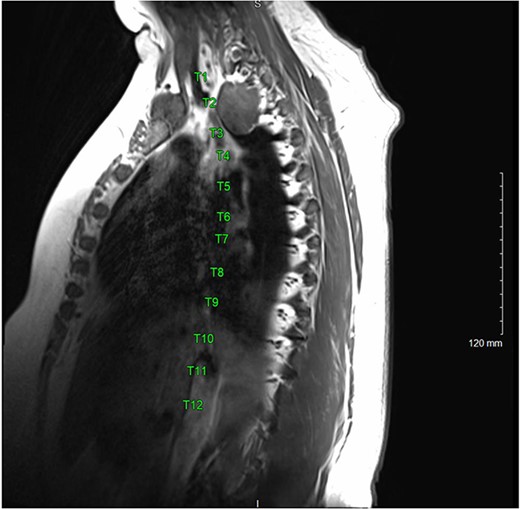

A 36-year-old female presented to an outside emergency department reporting chest pain, dizziness and abdominal pain for 7 hours. A computed tomography (CT) angiogram of the chest revealed a right paraspinal 4.2 × 2.8 × 3.3-cm cystic mass at the level of T2-3, which was well-circumscribed (Figs 1 and 2).

A magnetic resonance imaging (MRI) showed that the tumor extended into the outer aspect of the right T2-T3 neural foramen and could represent a nerve sheath tumor. Sixteen months later, neurosurgical consultation repeated her MRI, which showed that the mass had grown 2 mm (Figs 3 and 4). There was no extension into the neural foramen or bone erosion.